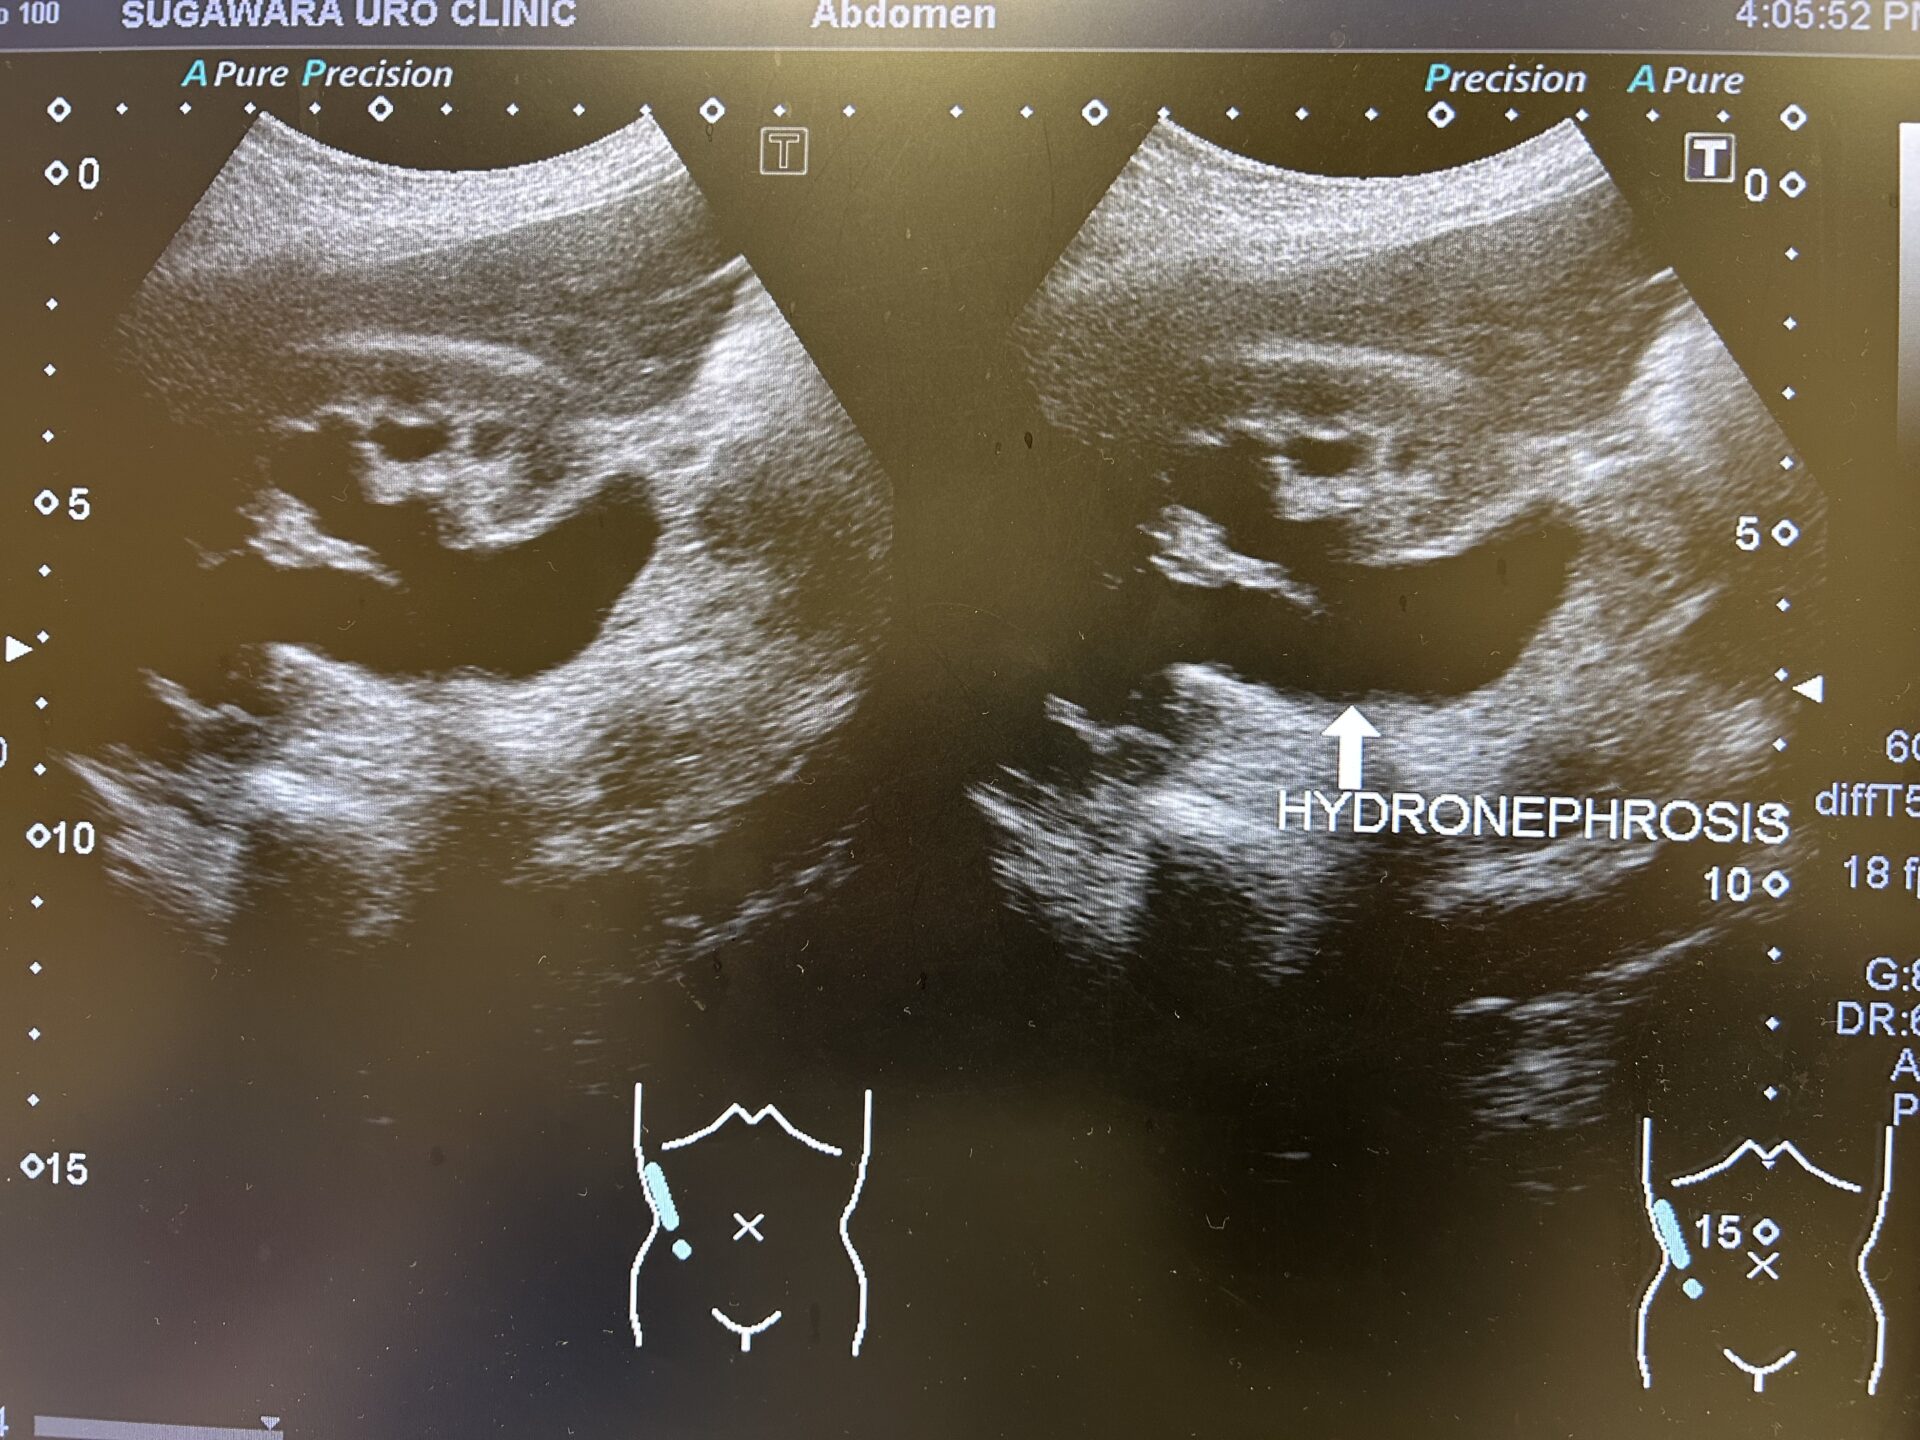

【今回発覚した右水腎症】

【半年前には右水腎症は認められていなかった】